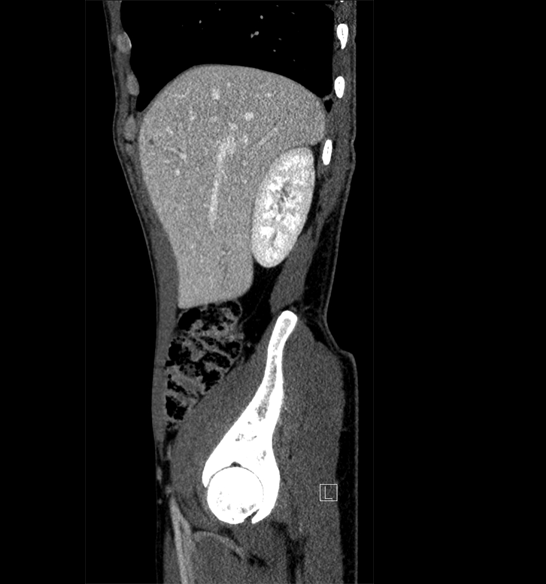

Body

Covers abdominal CT anatomy.